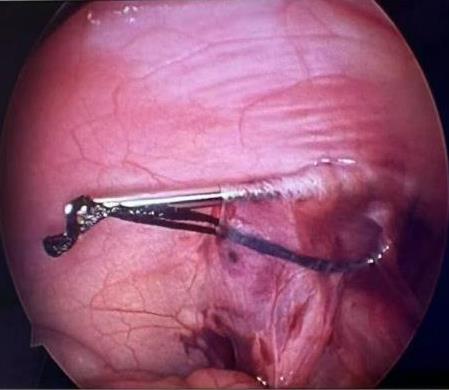

• 一次性子母胆道镜辅助内镜逆行阑尾炎治疗术对急性非复杂性阑尾炎的诊断和治疗价值分析

摘要:目的 探讨一次性子母胆道镜辅助内镜逆行阑尾炎治疗术在急性非复杂性阑尾炎治疗中的诊断和治疗价值。方法 回顾性分析2022年9月-2024年9月该院内镜中心通过一次性子母胆道镜辅助内镜逆行阑尾炎治疗术治疗的39例急性非复杂性阑尾炎患者的临床资料,观察内镜下表现、子母网篮取石率、阑尾支架置入率、技术成功率、临床成功率、手术时间、住院时间、并发症发生率和术后6 h视觉模拟评分法(VAS)评分,以及术后24 h炎症指标。结果 28例(71.8%)患者结肠镜下阑尾开口可见充血和水肿,10例(25.6%)患者结肠镜下阑尾开口可见脓液流出,32例(82.1%)患者子镜下阑尾腔内可见大量脓液,20例(51.3%)患者子镜下阑尾腔内可见粪石;一次性子母胆道镜辅助内镜逆行阑尾炎治疗术的技术成功率为100.0%(39/39);手术时间(21.08±7.49)min;住院时间(3.97±2.08)d;8例(20.5%)患者行内镜下子母网篮取石术;14例(35.9%)患者行阑尾支架置入术。临床成功率为97.4%(38/39),1例患者术后临床症状和炎症指标未缓解,转外科行阑尾切除术。38例患者术后6 h的VAS评分 < 3分,腹痛症状明显缓解;术后24 h白细胞计数和中性粒细胞百分比较术前明显下降,差异均有统计学意义(P < 0.05);39例患者均未发生并发症;术后随访(5.94±4.03)个月,3例(7.7%)出现复发。结论 一次性子母胆道镜辅助内镜逆行阑尾炎治疗术诊断和治疗急性非复杂性阑尾炎,安全且有效,值得临床推广应用。